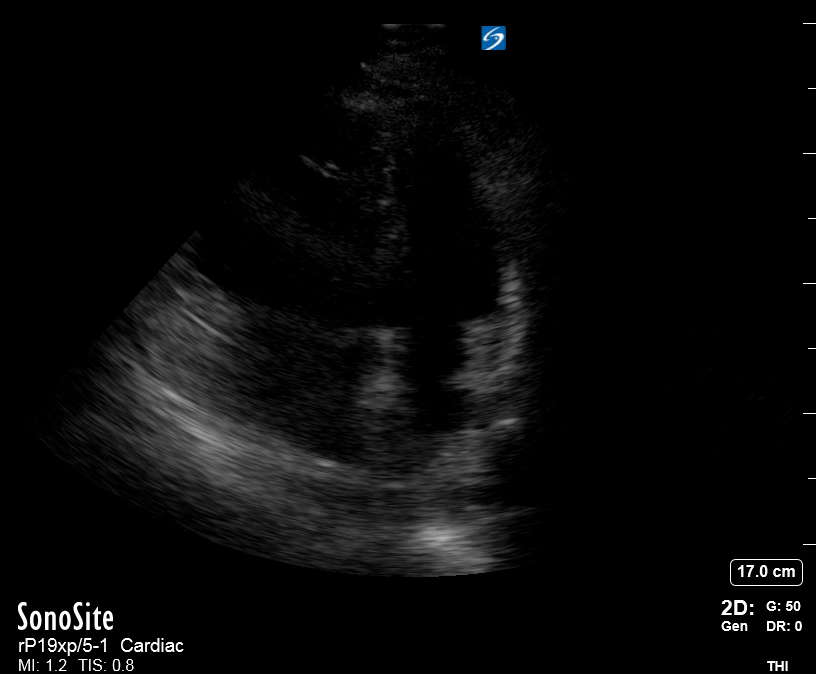

Effusion: is there a pericardial or pleural effusion?

Pericardial effusion is a continuum and can potentially evolve into haemodynamic collapse. Tamponade physiology is detectable earlier with ultrasound than with traditional physical examination, and it has been demonstrated that PoCUS improves mortality in penetrating cardiac trauma. Timely and accurate diagnosis is, therefore, vital.

THE VIEWS

The subxiphoid view is the most reliable for detecting pericardial effusion. Still, it is ideal to obtain different views not to miss a focal effusion as small amounts of fluid can lead to tamponade physiology. Tamponade does not link strictly to the size of the effusion, but correlates more with the speed of onset, causes, and haemodynamic effects.

PITFALLS & PLEURAL EFFUSIONS

A common error is to confuse a pericardial fat pad with effusion. Fatty tissue has a heterogeneous echotexture, moving in coordination with the myocardium, and it cannot be tracked around the heart, especially posteriorly and to the apex. Another pitfall is misinterpreting a pleural effusion as a pericardial effusion. However, they can be differentiated by their relationship to the descending aorta. Pericardial effusion may be seen between the aorta and the LV free wall, whereas pleural effusions are posterior to the descending aorta. Lastly, other causes, namely hypovolaemia and large pleural effusions, can cause RA and RV collapse.